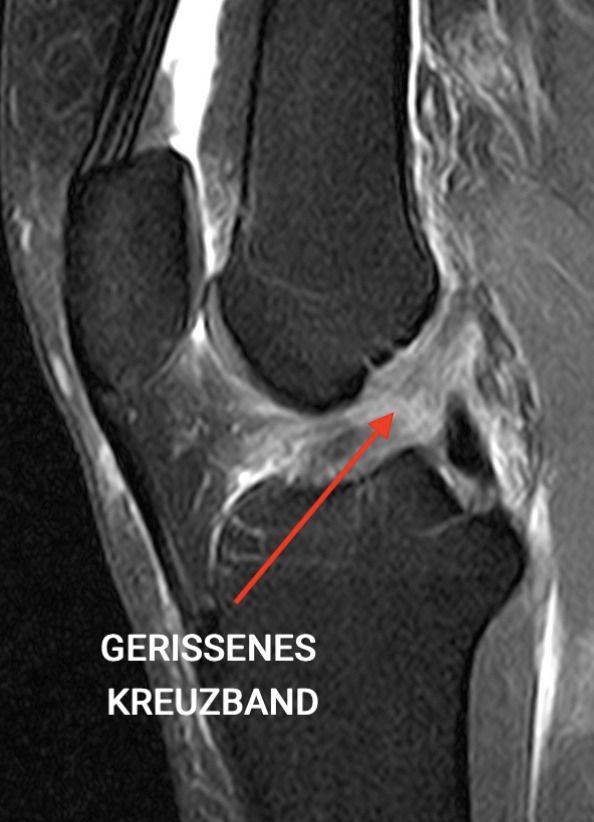

Verdacht erhärten mit einer MRT-Untersuchung Den Verdacht erhärten bedeutet, auch wenn die Kreuzbänder selbst nicht im Röntgenbild darstellbar sind, besteht die Möglichkeit, durch das Erkennen von knöchernen Veränderungen, die Verdachtsdiagnose eines Kreuzbandrisses zu stellen, und ggf Normalerweise verläuft das vordere Kreuzband gestreckt und parallel zur Blumensaatlinie, die dem Dach des Sulcus intercondylaris entspricht, und weist im Querschnitt eine ovale Form auf. Die Vorteile des MRT bei Knieverletzungen Der Vorteil des MRT liegt in der Präzisierung der Diagnose und vor allem der Fahndung nach eventuellen Begleitverletzungen

Kreuzbandriss MRT » Ablauf & Bilder Radiologie ARISTRA. Ein unfallbedingter Knorpelschaden, Seitenbandverletzungen oder ein Meniskusriss kann mithilfe des MRT dargestellt werden. Verdacht erhärten mit einer MRT-Untersuchung Den Verdacht erhärten bedeutet, auch wenn die Kreuzbänder selbst nicht im Röntgenbild darstellbar sind, besteht die Möglichkeit, durch das Erkennen von knöchernen Veränderungen, die Verdachtsdiagnose eines Kreuzbandrisses zu stellen, und ggf

Orthopädie in der Radiologie ARISTRA. Die Vorteile des MRT bei Knieverletzungen Der Vorteil des MRT liegt in der Präzisierung der Diagnose und vor allem der Fahndung nach eventuellen Begleitverletzungen Nach der MRT des Kreuzbandrisses findet ein abschließendes Gespräch mit einem Radiologen statt, der die Aufnahmen auswertet, Ihnen die Ergebnisse erklärt und die passenden Therapiemaßnahmen vorschlägt.